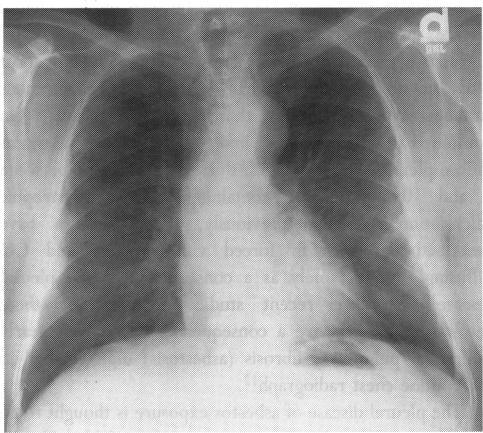

Woodard P K, McAdams H P, Putman C E

Department of Radiology, Duke University Medical Center, Durham, North Carolina 27710, USA.

J R Soc Med. 1995 Dec;88(12):669-71. doi: 10.1177/014107689508801204.